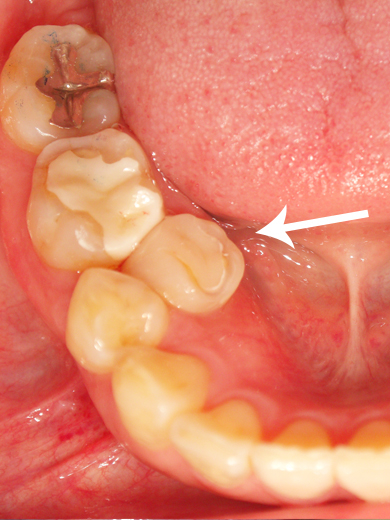

40代 女性 右下5 北葛城郡在住

![]() 〔術前〕 |